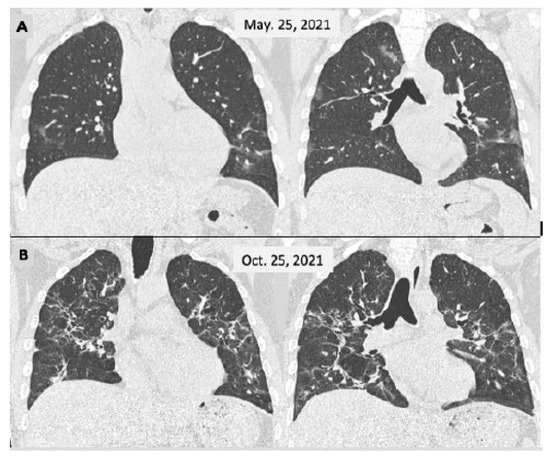

Figure 2.

Male, 46 y-o, admitted on 25 March 2021 with a fever and breathlessness. Their PCR test was positive for SARS-CoV-2. The CT scan (A) showed a few small and faint bilateral peripheral opacities, mainly in the lower lobes (moderate COVID-19); the patient was cared for as an outpatient. He persisted to have a fever for 2 weeks and displayed slow improvement over the next 2 months with a persistent cough. A second CT scan (B) was performed 5 months later showing more extensive lesions with sequelae appearance.